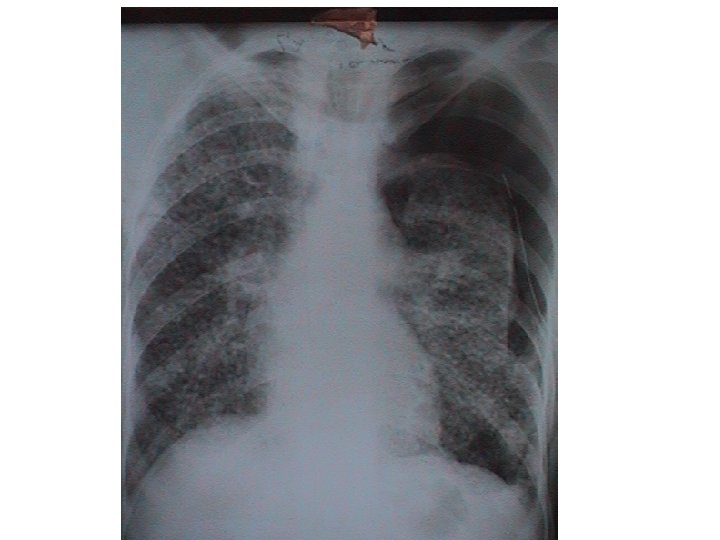

C- Miliaires des affections malignes : 1 - Lymphangite carcinomateuse (Métastase par voie lymphatique) : • Réalise une miliaire fébrile avec des images réticulomicronodulaires diffuses associées le plus souvent à des ADP médiastinales. 2 - Carcinose miliaire (métastase par voie hématogène) : • Miliaire atypique réalisant tous les aspects entre l’image micronodulaire et l’aspect en lâcher de ballon. 3 - hémoreticulopathie maligne : • Maladie de Hodgkin avec présence constante des ADP. • LMNH rarement responsables de miliaires.